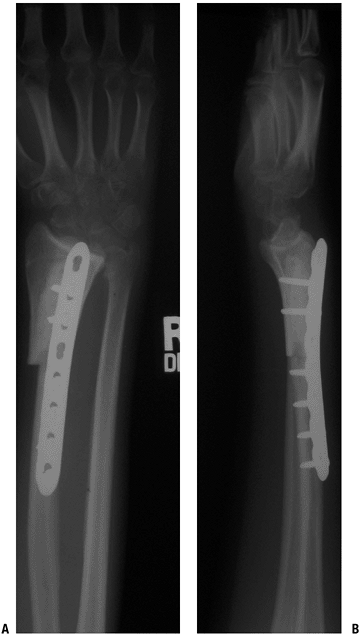

“Rejection” of transplanted bone does not occur, but role of “histocompatibility” is currently being evaluated.P.64 Figure 4.3-3 Figure 4.3-3

These early postoperative radiographs show an autograft nonvascularized

proximal fibula that has been used to reconstruct the defect following

resection of a distal radius for a giant cell tumor of bone. In this

case, the fibula was used to achieve an intercalary arthrodesis. A

proximal fibula may also be used with ligament reconstruction to

replace the distal radius and allow some wrist motion.![]() Figure 4.3-4 Radiographs of the proximal femur (A) and knee (B). Figure 4.3-4 Radiographs of the proximal femur (A) and knee (B).

An extra-articular resection of the distal femur was performed

secondary to extensive tumor extension into the knee joint. An

intercalary allograft fusion of the knee with a long intramedullary

fusion nail was performed.